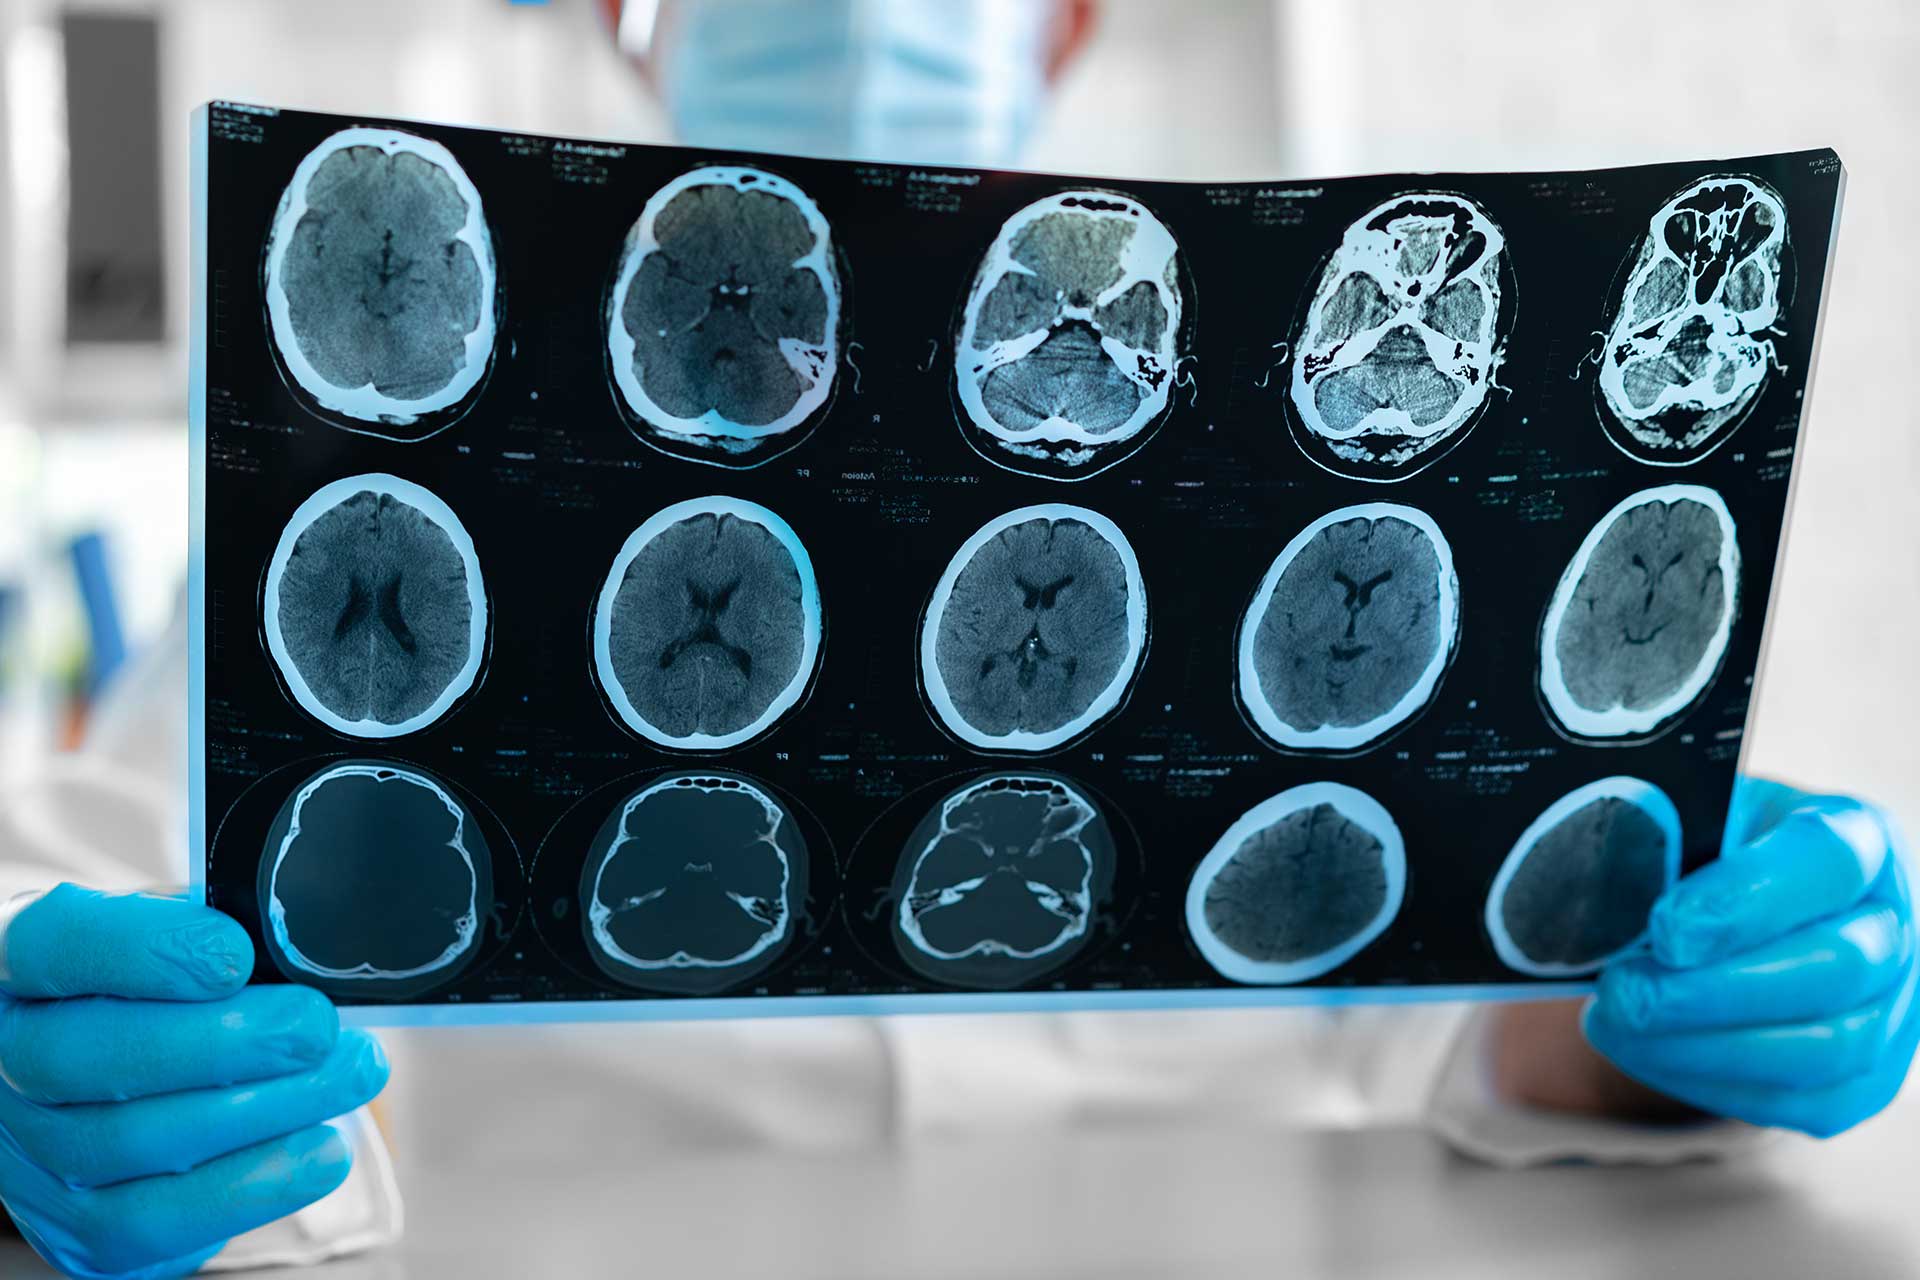

Diagnostic Services

ECG – Electrocardiograms for heart health Ultrasound/Sonar – General diagnostic imaging